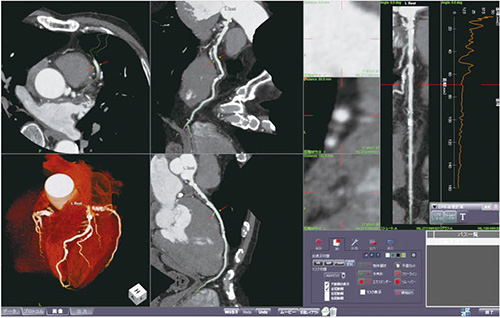

心臓CT検査では、ほとんどの場合において撮影終了後に画像処理を行い、診断を行う。数年前より、多くのワークステーションで撮影終了後の画像を読み込むことによって、自動的に冠動脈解析が行われる“冠動脈解析専用ソフト”が搭載されるようになった。ziostation2では、撮影終了後の画像を読み込むと、ほとんどの症例で診断に不要な胸骨や椎体などが除去された状態で、VRが自動的に作成される。また、大動脈、左冠動脈、右冠動脈、心筋と、各セグメンテーションを自動的に認識し保存される。認識されたセグメンテーションを選択・切り替えをするだけで、Angio Graphic ViewやTree VRなど、診療科や依頼医の要望に対しても新たに画像作成をせずに画像提供できる(図1)。

図1 冠動脈解析ソフト“CT冠動脈解析2”を起動した画面

1画面でさまざまな表示方法による観察が可能となっており、

画像作成時の負担低減に効果をもたらしている。